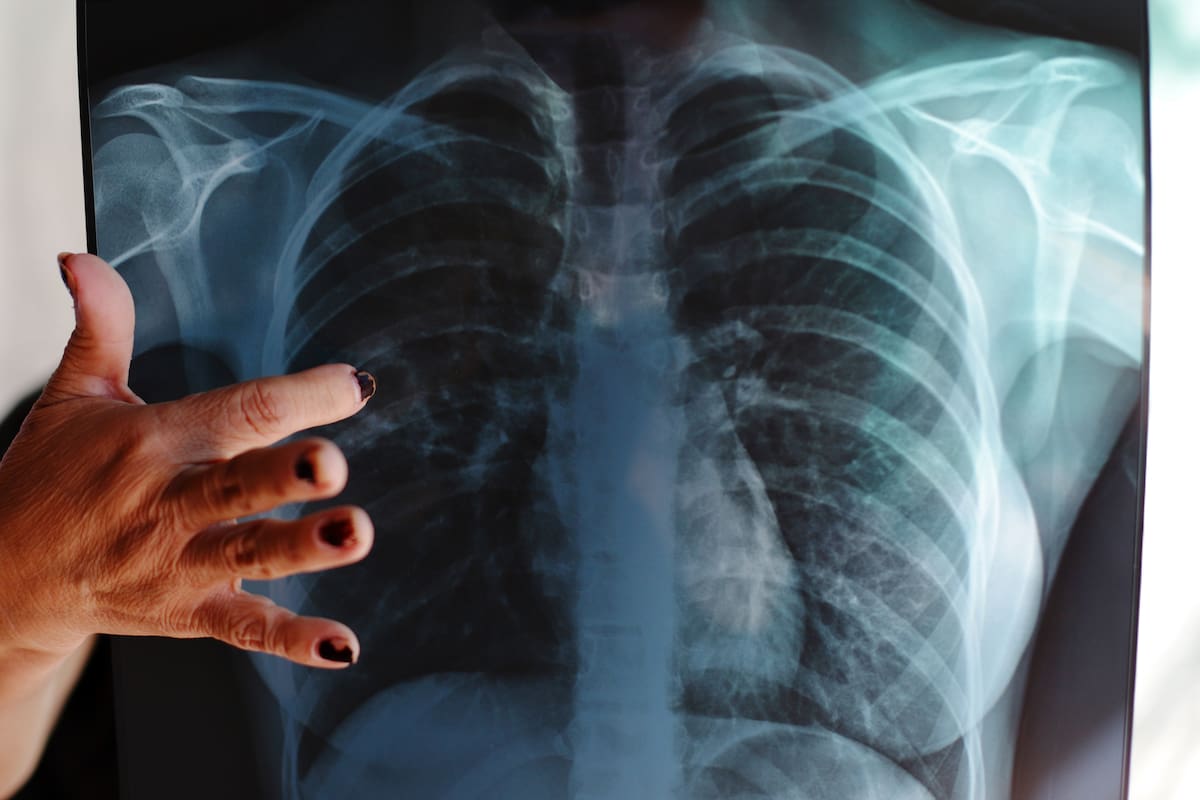

Mexicali, Baja California.- Hasta 3 mil casos nuevos de tuberculosis son los que se registran al año en Baja California, ocupando el primer lugar a nivel nacional como el estado con mayor número de contagios a lo largo del año.

En el marco del Día Mundial de la Tuberculosis, el secretario de Salud en el estado, José Adrián Medina Amarillas, declaró que por año llegan a fallecer entre 275 y 300 personas por tuberculosis, enfermedad que se transmite por vía aérea.